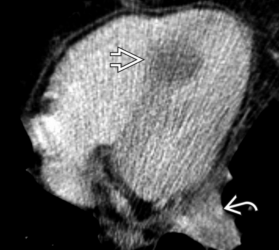

Metastases de mélanome VD et OD

Metastase myocardique melanome progressif